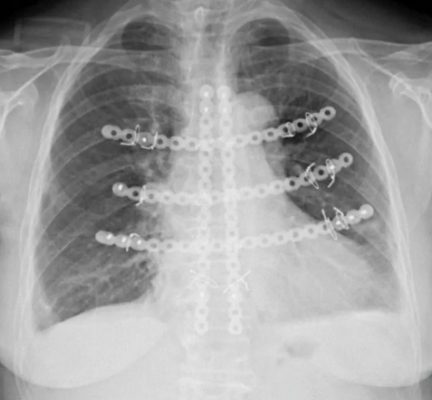

近日,广东医附院胸外科在梁柱主任、王志刚教授带领下,由胸壁外科亚专业负责人谢占强副主任医师完成一例高难度胸骨肿瘤切除+胸壁重建术。该手术采用了先进的MatrixRIB胸肋骨内固定系统,塑形更符合胸廓解剖特点,且稳定性可靠。

▲MatrixRIB胸肋骨内固定系统胸壁重建

胸骨切除术后用于胸廓重建移植物的吻合度和技术可行性一直是胸外科的难题。传统的材料在胸廓重建中也有一定的支撑作用,但传统材料在形状、功能、吻合度等方面都有局限性,且术后患者恢复较差,肺功能受到影响,在外观上也有影响,此手术的完成标志着我科胸壁肿瘤切除+胸壁重建术再上新台阶!